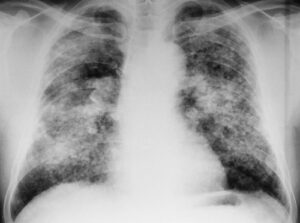

Пневмокониоз — это классическое профессиональное заболевание, которое включает несколько разновидностей, в том числе пневмокониоз. Обычно, собирая анамнез и анамнез жизни, врач может поставить диагноз уже без результатов первичного обследования. Антракноз встречается у шахтеров, которые постоянно контактируют с углем. Как распознать болезнь на ранней стадии и избежать осложнений — об этом расскажет сегодняшняя статья. Общая информация …

Рак легких считается наиболее распространенным видом рака, но его можно предвидеть и предотвратить. Это происходит по многим причинам, но наиболее распространенными являются воздействие табачного дыма, рабочая или домашняя пыль, а также некоторые сопутствующие заболевания. Их можно проследить в анамнезе большинства пациентов с раком легких, поэтому, чтобы избежать его развития, их воздействие на организм должно быть …